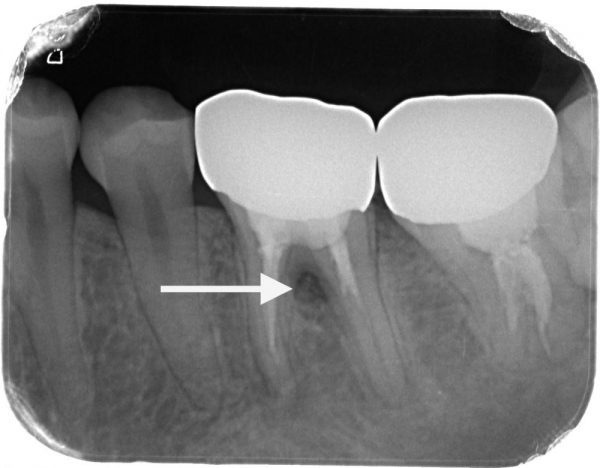

診査するためにレントゲンを撮りました。

この矢印の部分が黒くなっているのがわかると思います。

ここが黒くなる理由は、歯に穴が空いているか、ヒビが入っているか、歯周病が一般的には考えられます。

当院では、根管治療をする前にさまざまな診査を行いますが、診査をした結果、根尖性歯周炎とパーフォレーション(歯の内部の穴)と判断しました。

根尖性歯周炎は根の先に炎症がある状態です。この歯は、根の先に炎症があり、歯の内部に材料がしっかり入っていません。